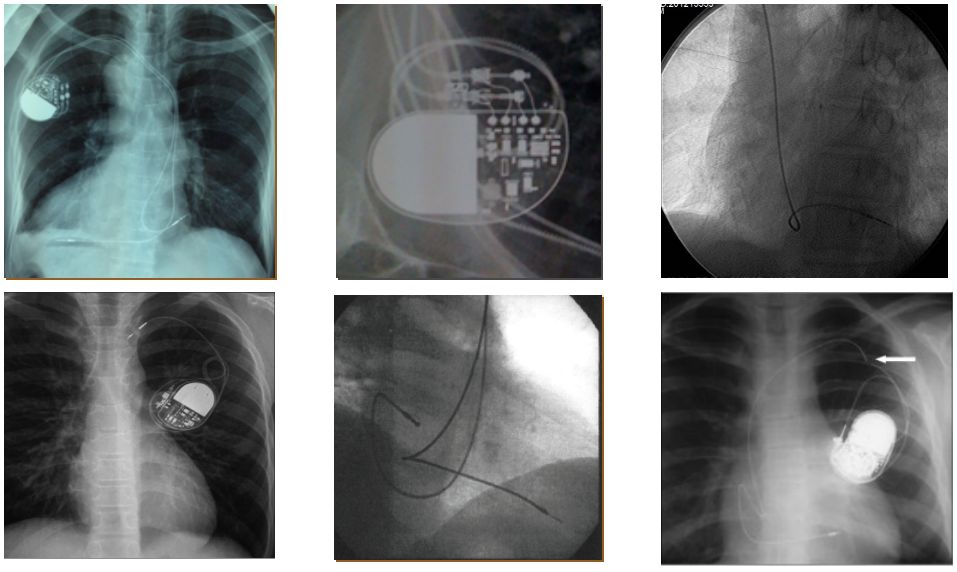

四、影像确认

X 光:脱位、穿孔、电极破裂、连接不良等;

心脏超声:穿孔,心包积液等;

为什么双极不起博起搏器故障怎么办?简单 5 步轻松搞定 | 上海心律失常论坛_https://www.jmylbn.com_新闻资讯_第13张

为什么双极不起博起搏器故障怎么办?简单 5 步轻松搞定 | 上海心律失常论坛_https://www.jmylbn.com_新闻资讯_第14张

图片来源:课件 PPT